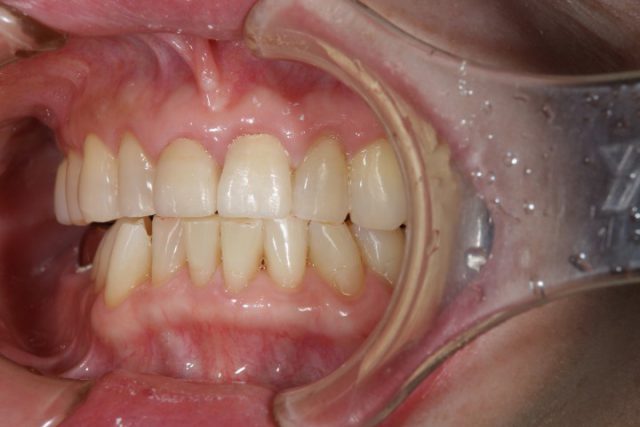

施術後

術後の画像を見ていただいても分かりますようにまわりの歯と比べてもとても自然に仕上がります。おそらく近くでじっと見られても被せものであるとは分からないほど自然です。患者さまご本人も被せ物の仕上がりにとても喜んでおられました。